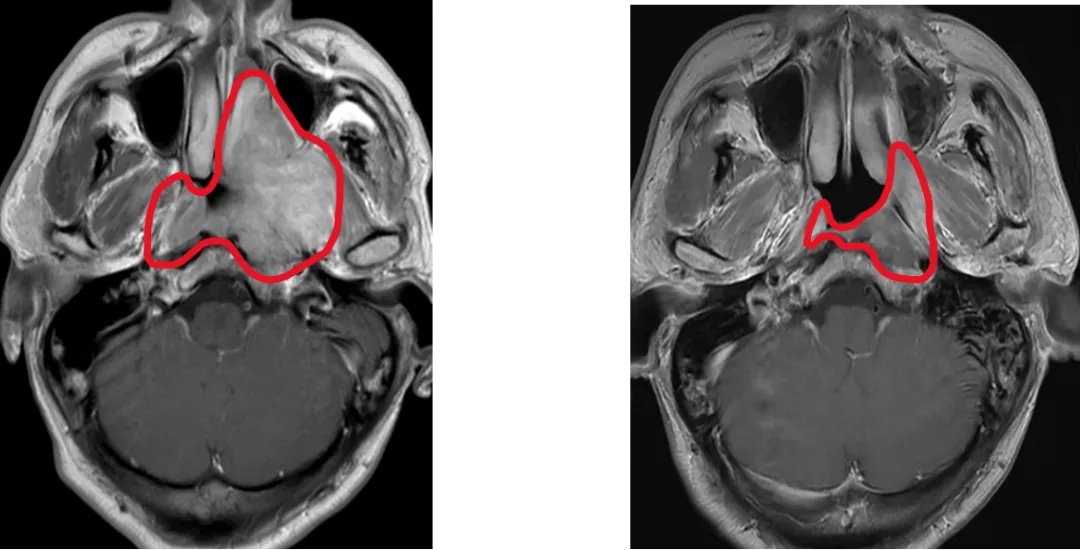

鼻咽癌高發于中國,新發病例占全球47%。放射治療是鼻咽癌的根治手段,但中晚期患者需要在放療前接受化療,放療前化療使90%患者腫瘤縮小,而既往國際指南推薦放療照射范圍仍需包括化療前腫瘤大小覆蓋的范圍,導致周圍正常組織(如內耳、腮腺)接受高劑量輻射,引發聽力損傷、口干等不可逆副作用,嚴重影響患者生活質量。

為此,馬駿院士團隊展開有關研究,采用了國際通用的標準多中心、隨機、平行對照設計,納入445例中晚期鼻咽癌患者,隨機分為兩組:分別基于化療后和化療前腫瘤范圍進行放療。主要終點為3年局部區域無復發生存率,次要終點包括毒副反應和生活質量。

這項多中心III期臨床試驗證實,僅照射化療后的腫瘤范圍,并沒有增加復發,卻顯著降低了毒副反應,顯著改善患者生活質量,使我國鼻咽癌診療實現從“保生存”到“優生存”的跨越式突破。3年局部區域無復發生存率達91.5%(與傳統療法持平);嚴重放射性口腔黏膜炎降低4成,晚期嚴重中耳炎發生率銳減5成,口干癥狀改善6成;整體健康狀態、體力狀態、情緒功能顯著改善,口干及唾液黏稠癥狀減輕。